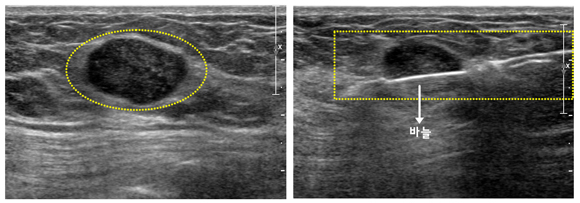

총 생검은 피부에 부분 마취를 한 후 굵은 바늘(14-18게이지)을 장착한 생검용 장비를 사용하여 병변 부위에 바늘을 대고, 용수철 기능을 이용해 총을 쏘듯이 방아쇠를 눌러 바늘이 자동으로 조직의 일부를 떼어내게 하는 간단한 방법입니다. 여러 번 조직을 채취하는 생검 방법으로 5회 정도 반복 시행합니다. 합병증으로 출혈, 통증, 염증, 흉벽 손상 등이 있을 수 있습니다.

[ 초음파 유도하 자동총 중심생검 ]

[ 총생검 초음파 사진과 총생검 시술 사진 ]